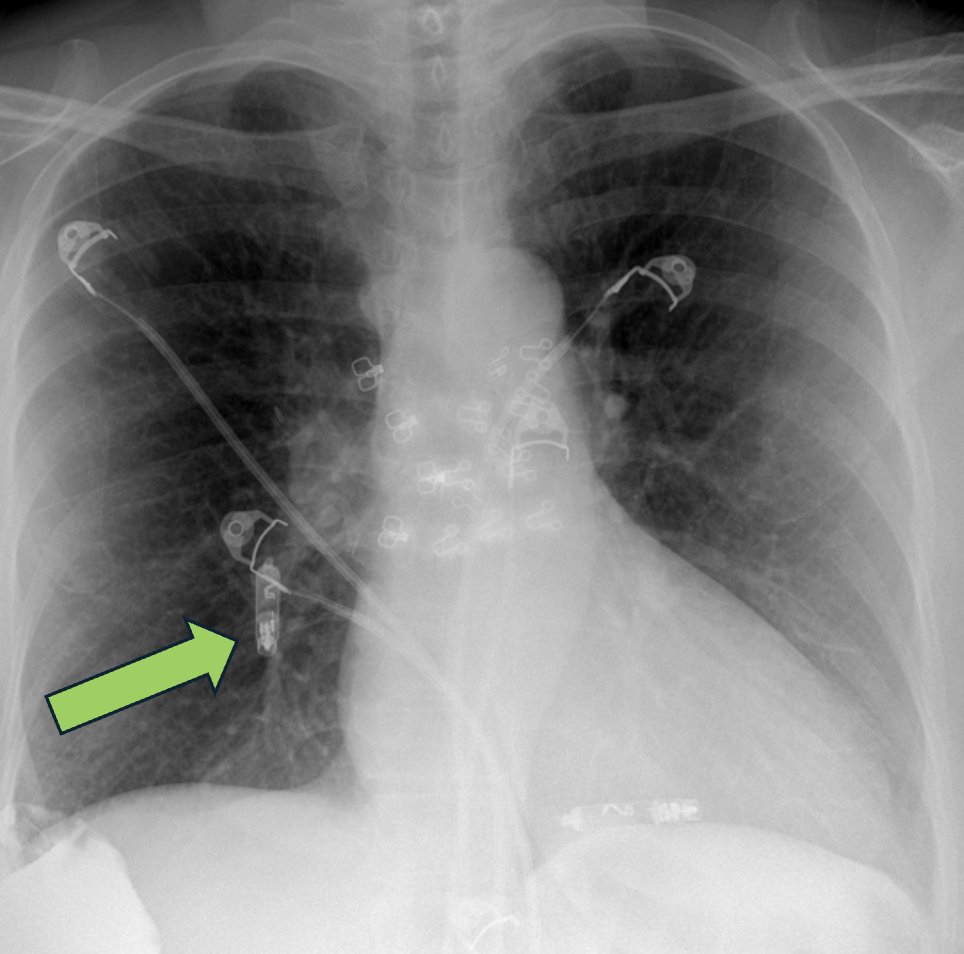

🫀Answer: Embolized right atrial leadless pacemaker! 🦓Uncommon complication, usually peri-procedural 🚧More common in patients with high BMI, tricuspid regurgitation, and atrial dilation 🥅Next step is retrieval of device with snare ❓Would you have caught this on first pass?

🚨Challenging case alert! 👩‍🦳72yo woman presents with acute dyspnea following dual-chamber leadless pacemaker placement. ➡️What is the device shown and is it in the correct location? #Radiology #Cardiology #Medtwitter #Radres

🫀✅ Answer: Micra leadless pacemaker⚡️ 📍Typically implanted in the right ventricle (via femoral venous access) 🔑 Imaging clue: small capsule-shaped device overlying the cardiac silhouette with small spider-like "fixation tines" Bonus pearl: if you see it somewhere that’s

🫀📷 Unknown device time… Spotted on CXR: a tiny metallic “capsule” overlying the heart 📷 👀What cardiac device is this? Bonus: where is it typically implanted? Drop your guess 👇 #Radiology #Cardiology #CXR #MedTwitter #Radres